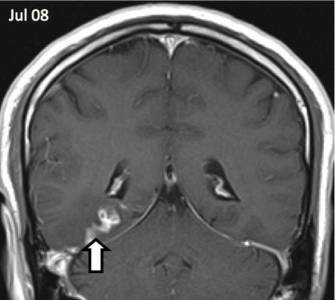

Ez az első alkalom a férfi megfordult, hogy az orvosok négy évvel ezelőtt, ő fejfájásra panaszkodott, és furcsa szagot. Az orvosok, akik végzett felmérés, megzavarodtak kóros területeket az agyban, hogy az MRI kimutatta. Megfigyelések a következő években azt mutatta, hogy a rendellenesség által mozgatott öt centiméter, írja a The Guardian.

Az orvosok a St. Thomas Kórház beteg HIV-tesztet, a szifilisz és a különböző fertőző betegségek. Ennek eredményeként, a biopszia jelenlétét mutatta galandféreg. Genetikai Wellcome Trust Sanger Institute Cambridge megállapítottuk, hogy ez egy rendkívül ritka parazita ismert Spirometra erinaceieuropaei.